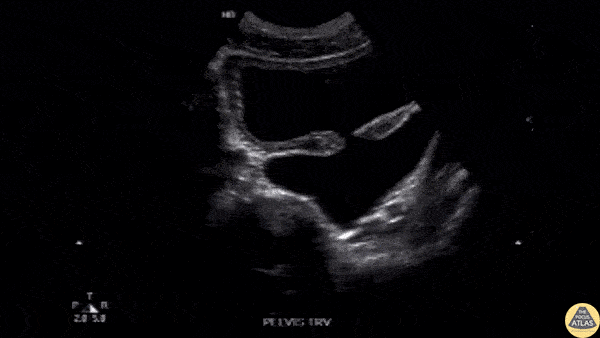

Renal/GU - Bladder Diverticulum

An elderly male presented to the ED following a MVA. Imaging revealed a pelvic fracture. During a FAST exam, the transverse pelvic view revealed a bladder diverticulum. Image courtesy of Robert Jones DO, FACEP @RJonesSonoEM Director, Emergency Ultrasound; MetroHealth Medical Center; Professor, Case Western Reserve Medical School, Cleveland, OH View his original post here